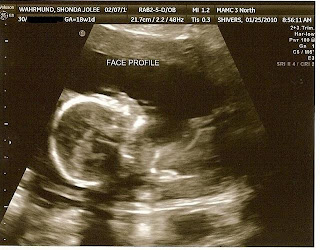

Boy or Girl?

Looks like a mini-Jay already

I am 18 weeks and today I had the "big" ultrasound.  I am happy to know that baby appears healthy with all it's limbs and organs functioning as expected.  I had intended on finding out the sex, but since Jay wants to wait til the baby is born we compromised.  I had the tech put the results in a sealed envelope to be opened once Jay deploys in April.  At that time I can really start planning and he will never know :)  Won't be able to post it on the blog because Jay reads the blog when he's away....but everyone will know soon enough!  June 21 is the big day.  I guess with our third child, it's only fitting he/she will arrive on the longest day of the year!  A sign of what our days will be like once we are outnumbered....LONG!  Only five more months to go and I am getting really excited.